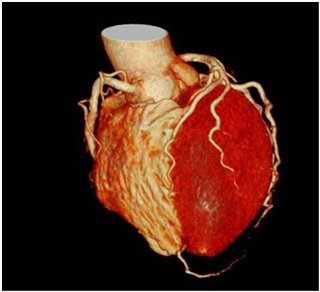

マルチスライスCT装置は、短時間で広範囲を撮影することができ、息を止めていただく時間が短いため、患者さんにとってより優しい検査が行えます。また、データ量が多く、高精細な3D画像、血管像、任意の断面像を作ることができます。

2管球CTでは、46cmの長さを1秒で撮影できる速さを持ち、息止めの困難な患者さんや、動きの速い心臓の撮影にとても強い装置です。また、低管電圧を活用して放射線被ばくを減らし、造影剤の使用量も抑えて検査することが可能となりました。

心臓血管3D画像